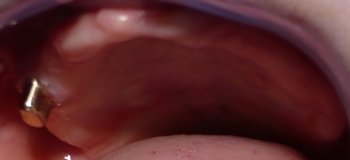

V spodnji čeljusti smo na edinem preostalem zobu izdelali koreninsko kapico, ki skrbi za boljšo stabilizacijo proteze. |

Ležišče na protezi, kamor se prilega koreninska kapica. |